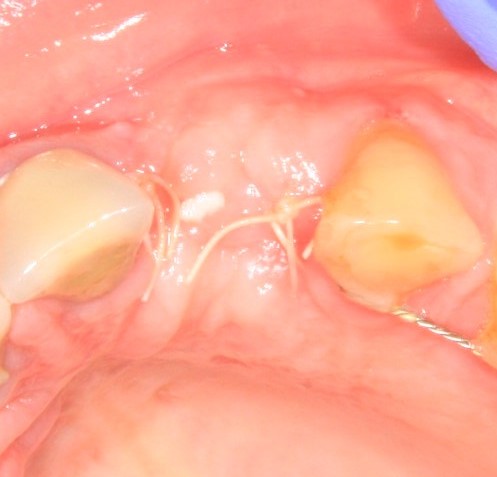

Разумеется, чтобы зафиксировать на имплантат коронку, необходимо его открыть. Затем,дождаться эпителизации десны вокруг его соединительной части. Для этого используются формирователи десны:

В начальной стадии процесс формирования десны занимает около двух недель. После чего мой друг Давид приступает к изготовлению временной коронки. «Временной», потому что нужно доформировать десну и решить проблемы с соседними зубами. Ведь нет ничего хуже, чем сначала подгонять постоянные коронки под существующие зубы, а потом — существующие зубы под уже установленные постоянные коронки. Всегда лучше делать всё в комплексе. Так рациональнее и выгоднее.